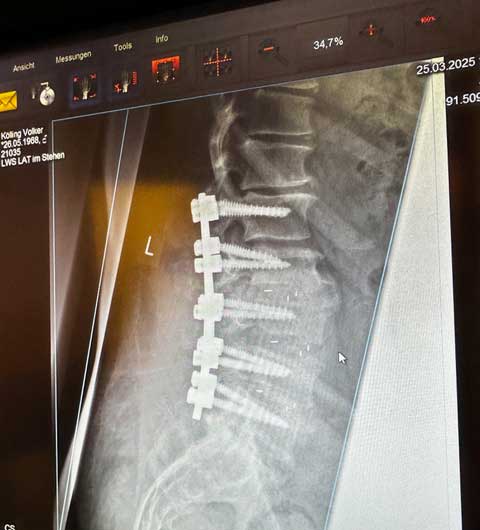

Seit Mai 2023 macht die Wirbelsäule nicht mehr mit: Erst klemmte die Halswirbelsäule den rechten Arm weg und dann kam die Lendenwirbelsäule hinterher. Nach einer Riesen-OP Im Februar 2025 ist die Gehfähigkeit weg. Kurzum: Die Geschäfte von Volker Kölling coast Communication ruhen. Projekt-Anfragen werden gerne an fähige Kollegen weitergeleitet. Danke für die tollen Jahre!